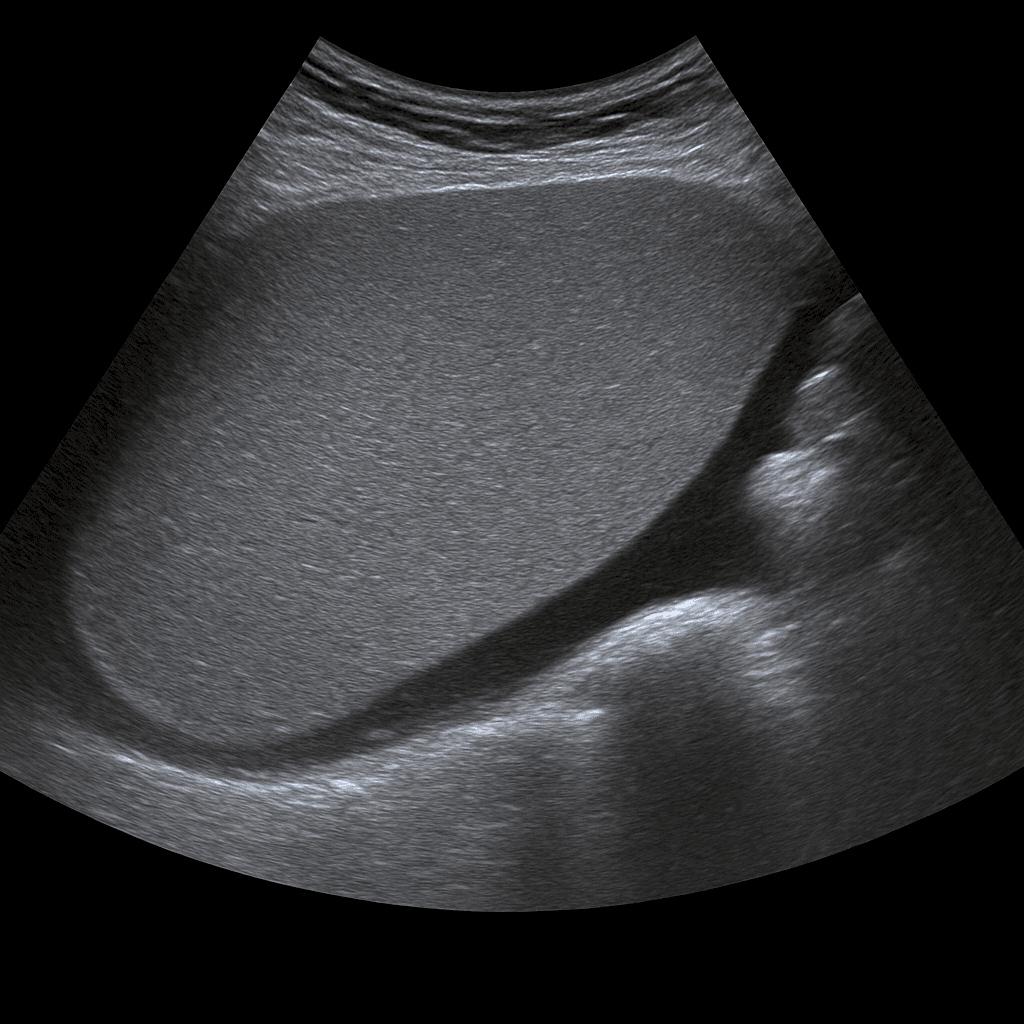

A spleen ultrasound is used to examine the size, shape, tissue structure and blood flow of the spleen. The examination is performed by a specialist in radiology and provides detailed images in real time that can show signs of enlargement, cysts, infarctions or other changes. Spleen ultrasound is often used to investigate the cause of abdominal pain, infection, anemia, suspected enlarged spleen (splenomegaly) or as part of an investigation of liver and blood diseases.

The examination is performed while you lie on your back or on your right side. A gel is applied to the skin and the doctor moves the ultrasound probe over the area under the left rib cage. The spleen is imaged from different angles to assess size, tissue and vascular flow. If necessary, the liver and kidney on the left side can also be examined for comparison.